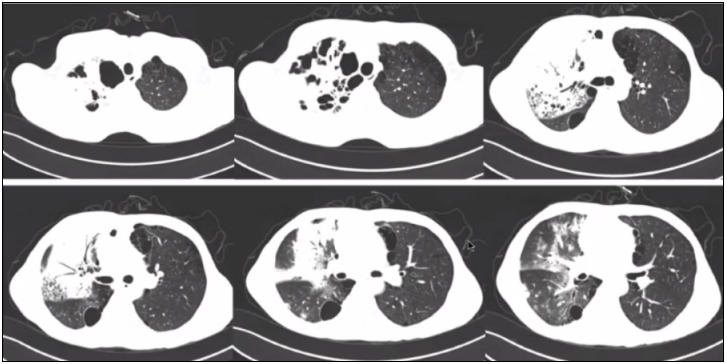

TSM的影像学表现多种多样。

病例1:患者53岁,主诉反复咳嗽、发作性喘息5月余,加重伴发热5 d。临床表现没有特异性,肺部影像学可见多发结节,有些结节靠近胸膜下,但无明显晕征,有大片实变影,其中可见支气管气象。纵隔窗可见结节及实变影,并未出现明显增强10

图片

图10  TSM患者肺部影像学表现

病例2:女性患者,62岁,反复咳嗽、咯血6年,加重1年。胸部CT可见轻度支气管扩张,肺部病灶不明显,仅有散在的一些小结节样改变及部分粟粒结节(图11)。通常我们认为这就是支气管扩张合并感染,更多会考虑排查结核菌、NTM及诺卡菌,但此例患者BALF培养及BALF NGS均提示马尔尼菲篮状菌。

图11  TSM患者肺部影像学表现

病例3:男性患者,50岁,反复咳嗽、咳痰2月余,胸痛1个月,发热2周。胸部CT示右上肺大片实变影,其内可见支气管气象,且出现坏死,肺结构破坏,下肺有大片散在斑片影(图12)

图12  TSM患者肺部影像学表现